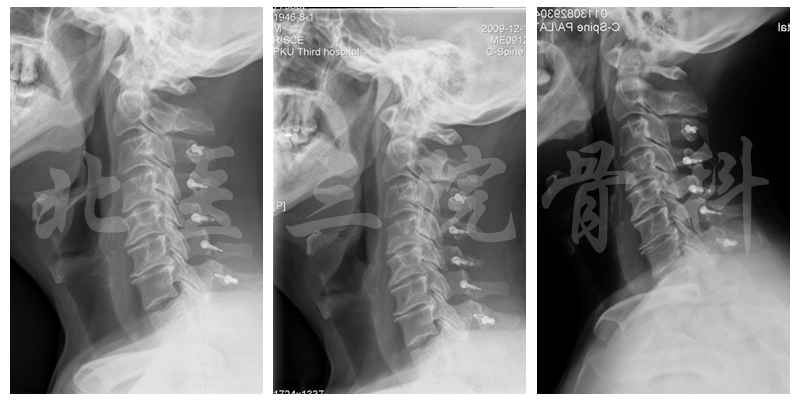

椎管测量

随访情况,Pre-op:VAS-neck: 3、mJOA: 12.5

随访时影像学检查